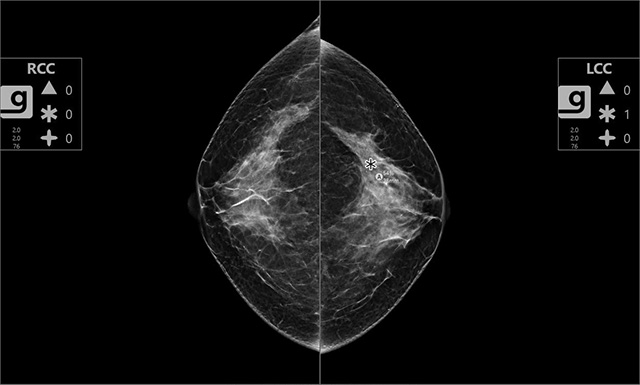

• 유방 영상 판독 보조 솔루션 Genius AI 2.0, 왼쪽 유방에서 발견된 병변의 위험도를 평가한 사진  /사진 제공=동아대병원

▲ 유방 영상 판독 보조 솔루션 Genius AI 2.0, 왼쪽 유방에서 발견된 병변의 위험도를 평가한 사진 /사진 제공=동아대병원